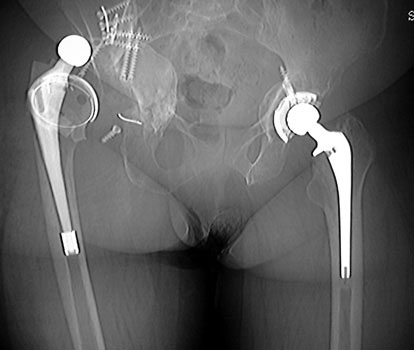

Dislocated total hip replacement

Dislocated femoral component secondary to loose acetabular cup

with reverse acetabular inclination